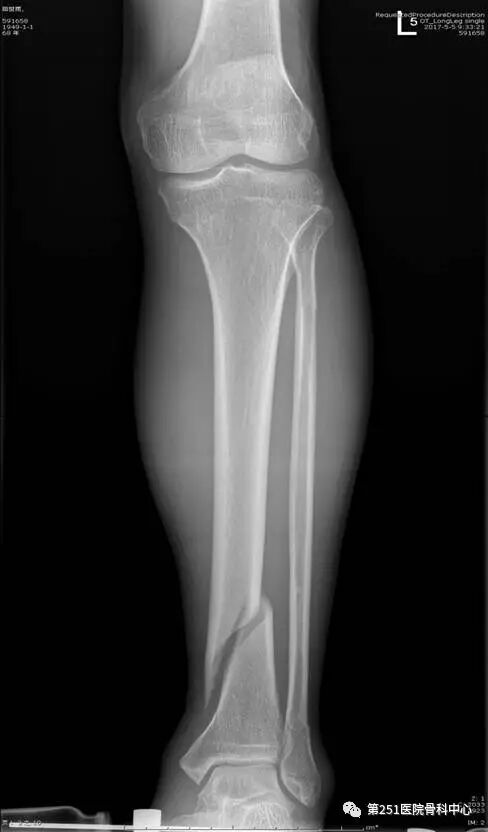

病例1:男性,40岁,车祸伤,胫腓骨多段骨折。